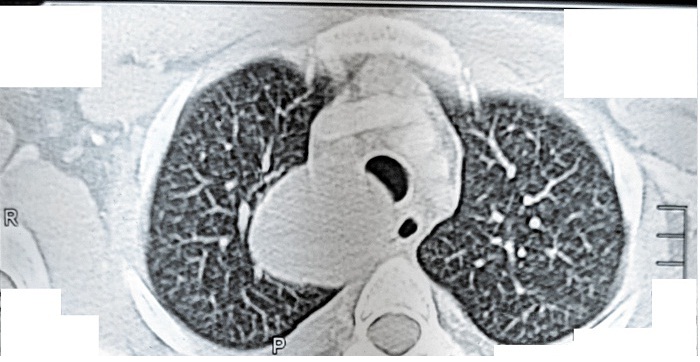

Figure 2. CECT of the chest showing a round homogenous cystic lesion in the right paratracheal region pressing on the esophagus and trachea.

A 16-year-old boy presented with chest pain for the previous seven days that was more on the right side, gradual in onset, dull in character, intermittent, and radiating to the back. It was aggravated on exertion and was relieved with rest. The pain was associated with shortness of breath. The patient also complained of dysphagia, which was occasional and progressive. There was no history of cough or recent chest infection. General physical and systemic examinations were unremarkable. He had a low-grade fever with a hemoglobin of 13.5 g/dl, white cell count of 12.4/dL, and ESR of 52. Other routine lab investigations were within normal limits. His chest x-ray showed a right mediastinal round opacity on the right side of the carina. On his CECT scan Chest, the authors found a well-marginated nonenhancing thick fluid-attenuating lesion centered at the right paratracheal location in the middle and posterior mediastinum on the right side that was pressing on the esophagus and trachea.